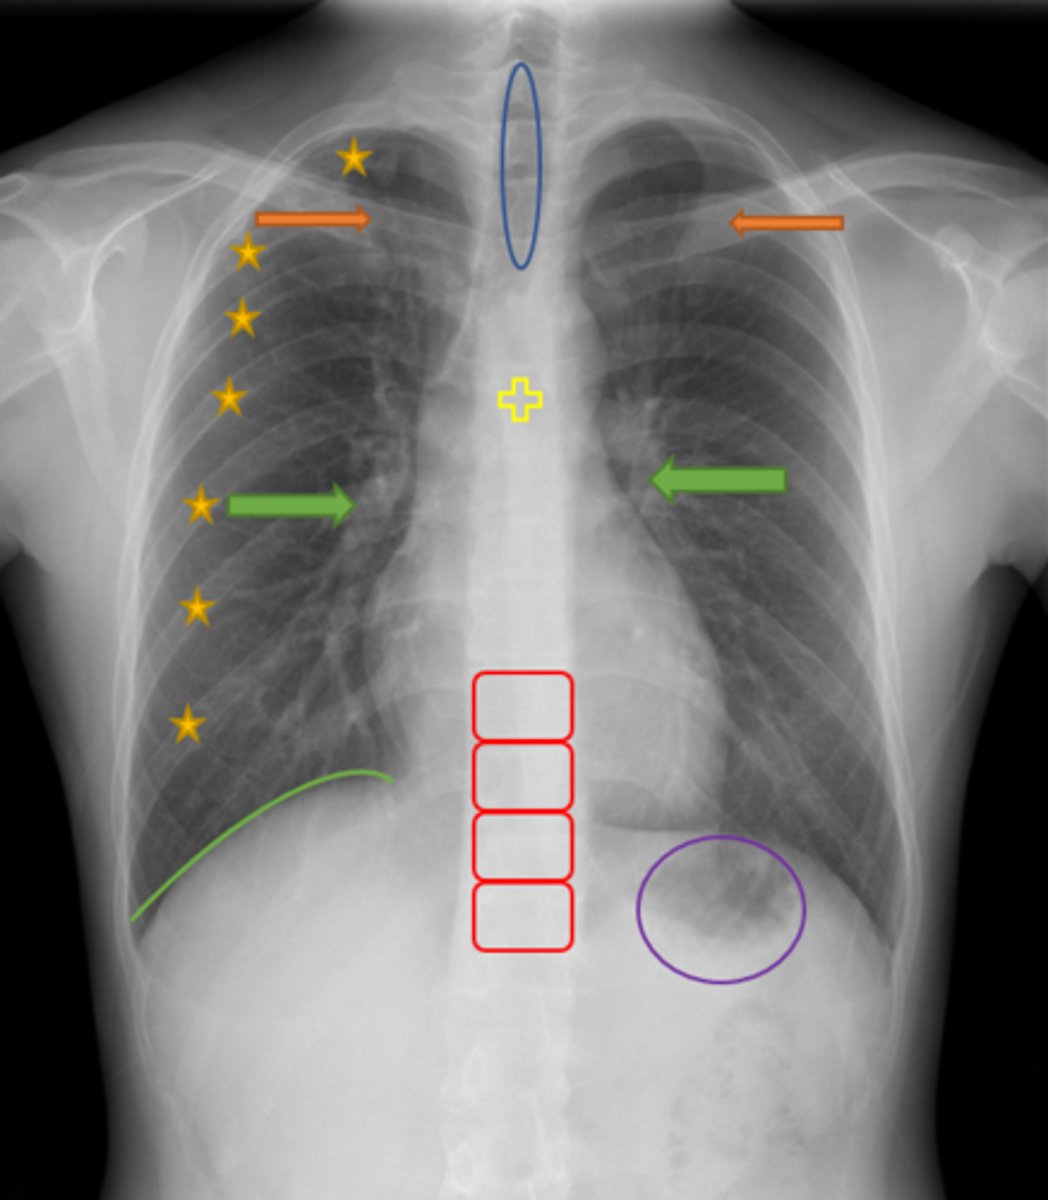

Aortic knob/arch

Pink Arrow

Left ventricle and border of the heart

Purple Line

Pulmonary arteries

Blue Arrows

Normal film

Interpretation

Trachea

Blue Oval

Pulmonary arteries

Green Arrows

Vertebrae/spine

Red Blocks

Clavicle

Orange Arrows

Ribs

Yellow Stars

Diaphragm

Green Line

Gastric bubble/stomach

Purple Circle

Carina

Yellow Cross